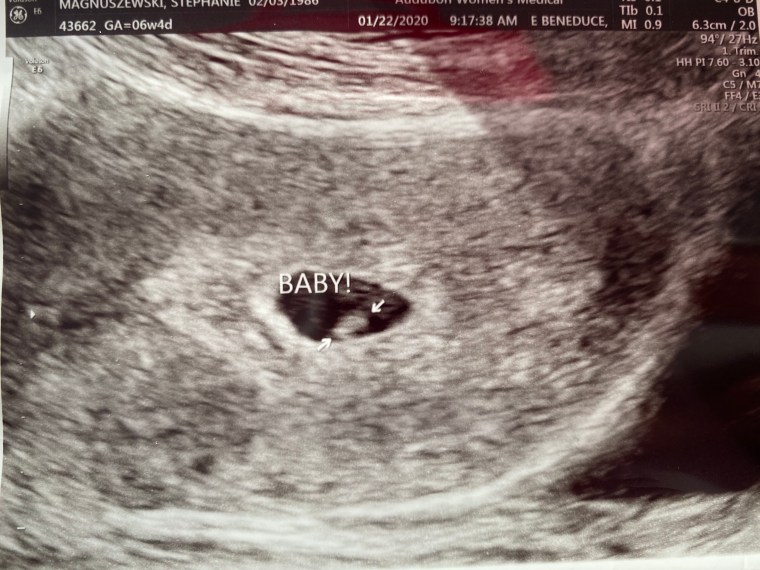

I called my doctor the next morning and she sent me for blood work, everything came back positive and numbers looked good. 48 hours we repeated the blood work and everything more then doubled. Because of my history of miscarriage they did have me in for an early ultrasound the following week at week 7, we were measuring a little behind where we should have been, so 10 days later we got a second ultrasound just to check on the growth and they were happy with everything. I was supposed to come in at 10 weeks for my first “official” appointment, but we were traveling and so it was postponed until today, I’m actually 11 weeks 5 days and of course we had a major snow storm blow in last night, so everything is closed today. So we’ll probably be over 12 weeks by the time I get in to see them now.

I’ll finish with a sono pic that we had done already and the only two bump pictures I’ve been bothered to take so far. Hopefully now that I’m back to blogging I’ll get a little better at taking them.